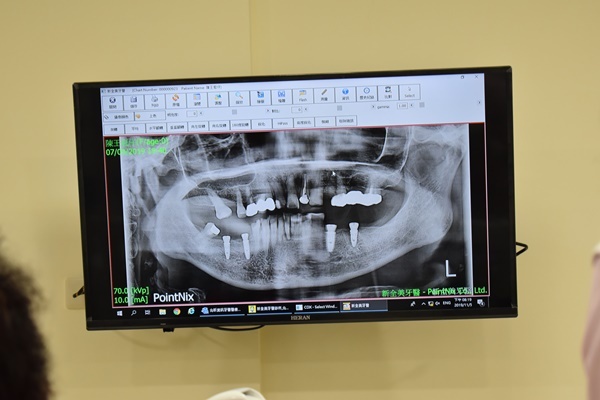

終於輪到我了!滿懷期待的我雀躍的步入診間,褪下口罩讓朱裕華醫師檢查我植牙失敗的部位,朱裕華醫師洗完我的牙齒並看了一眼我的口腔x光片表示:我植牙失敗的部位是埋入牙釘所造成的,牙釘其實是牙齒根管治療後為了不讓根管後的牙齒鬆動,用來固定的牙齒的醫材但為甚麼會當作植牙植體植入你的口腔實在令我匪夷所思,一定是不肖牙醫為了壓低植牙價格才會做出的黑心事!

聽到這裡我不禁紅了眼眶,只怪自己當初貪小便宜…朱裕華醫師表示植牙都會有植牙有專屬的植體,羊毛出在羊身上,價格比市面上便宜太多的植體一定有問題!我點點頭表示贊同!也向朱裕華醫師表示我想要再一次植牙!

評估完口腔及牙齒的狀況,朱裕華醫師向我表示我的條件是可以再一次植牙的!